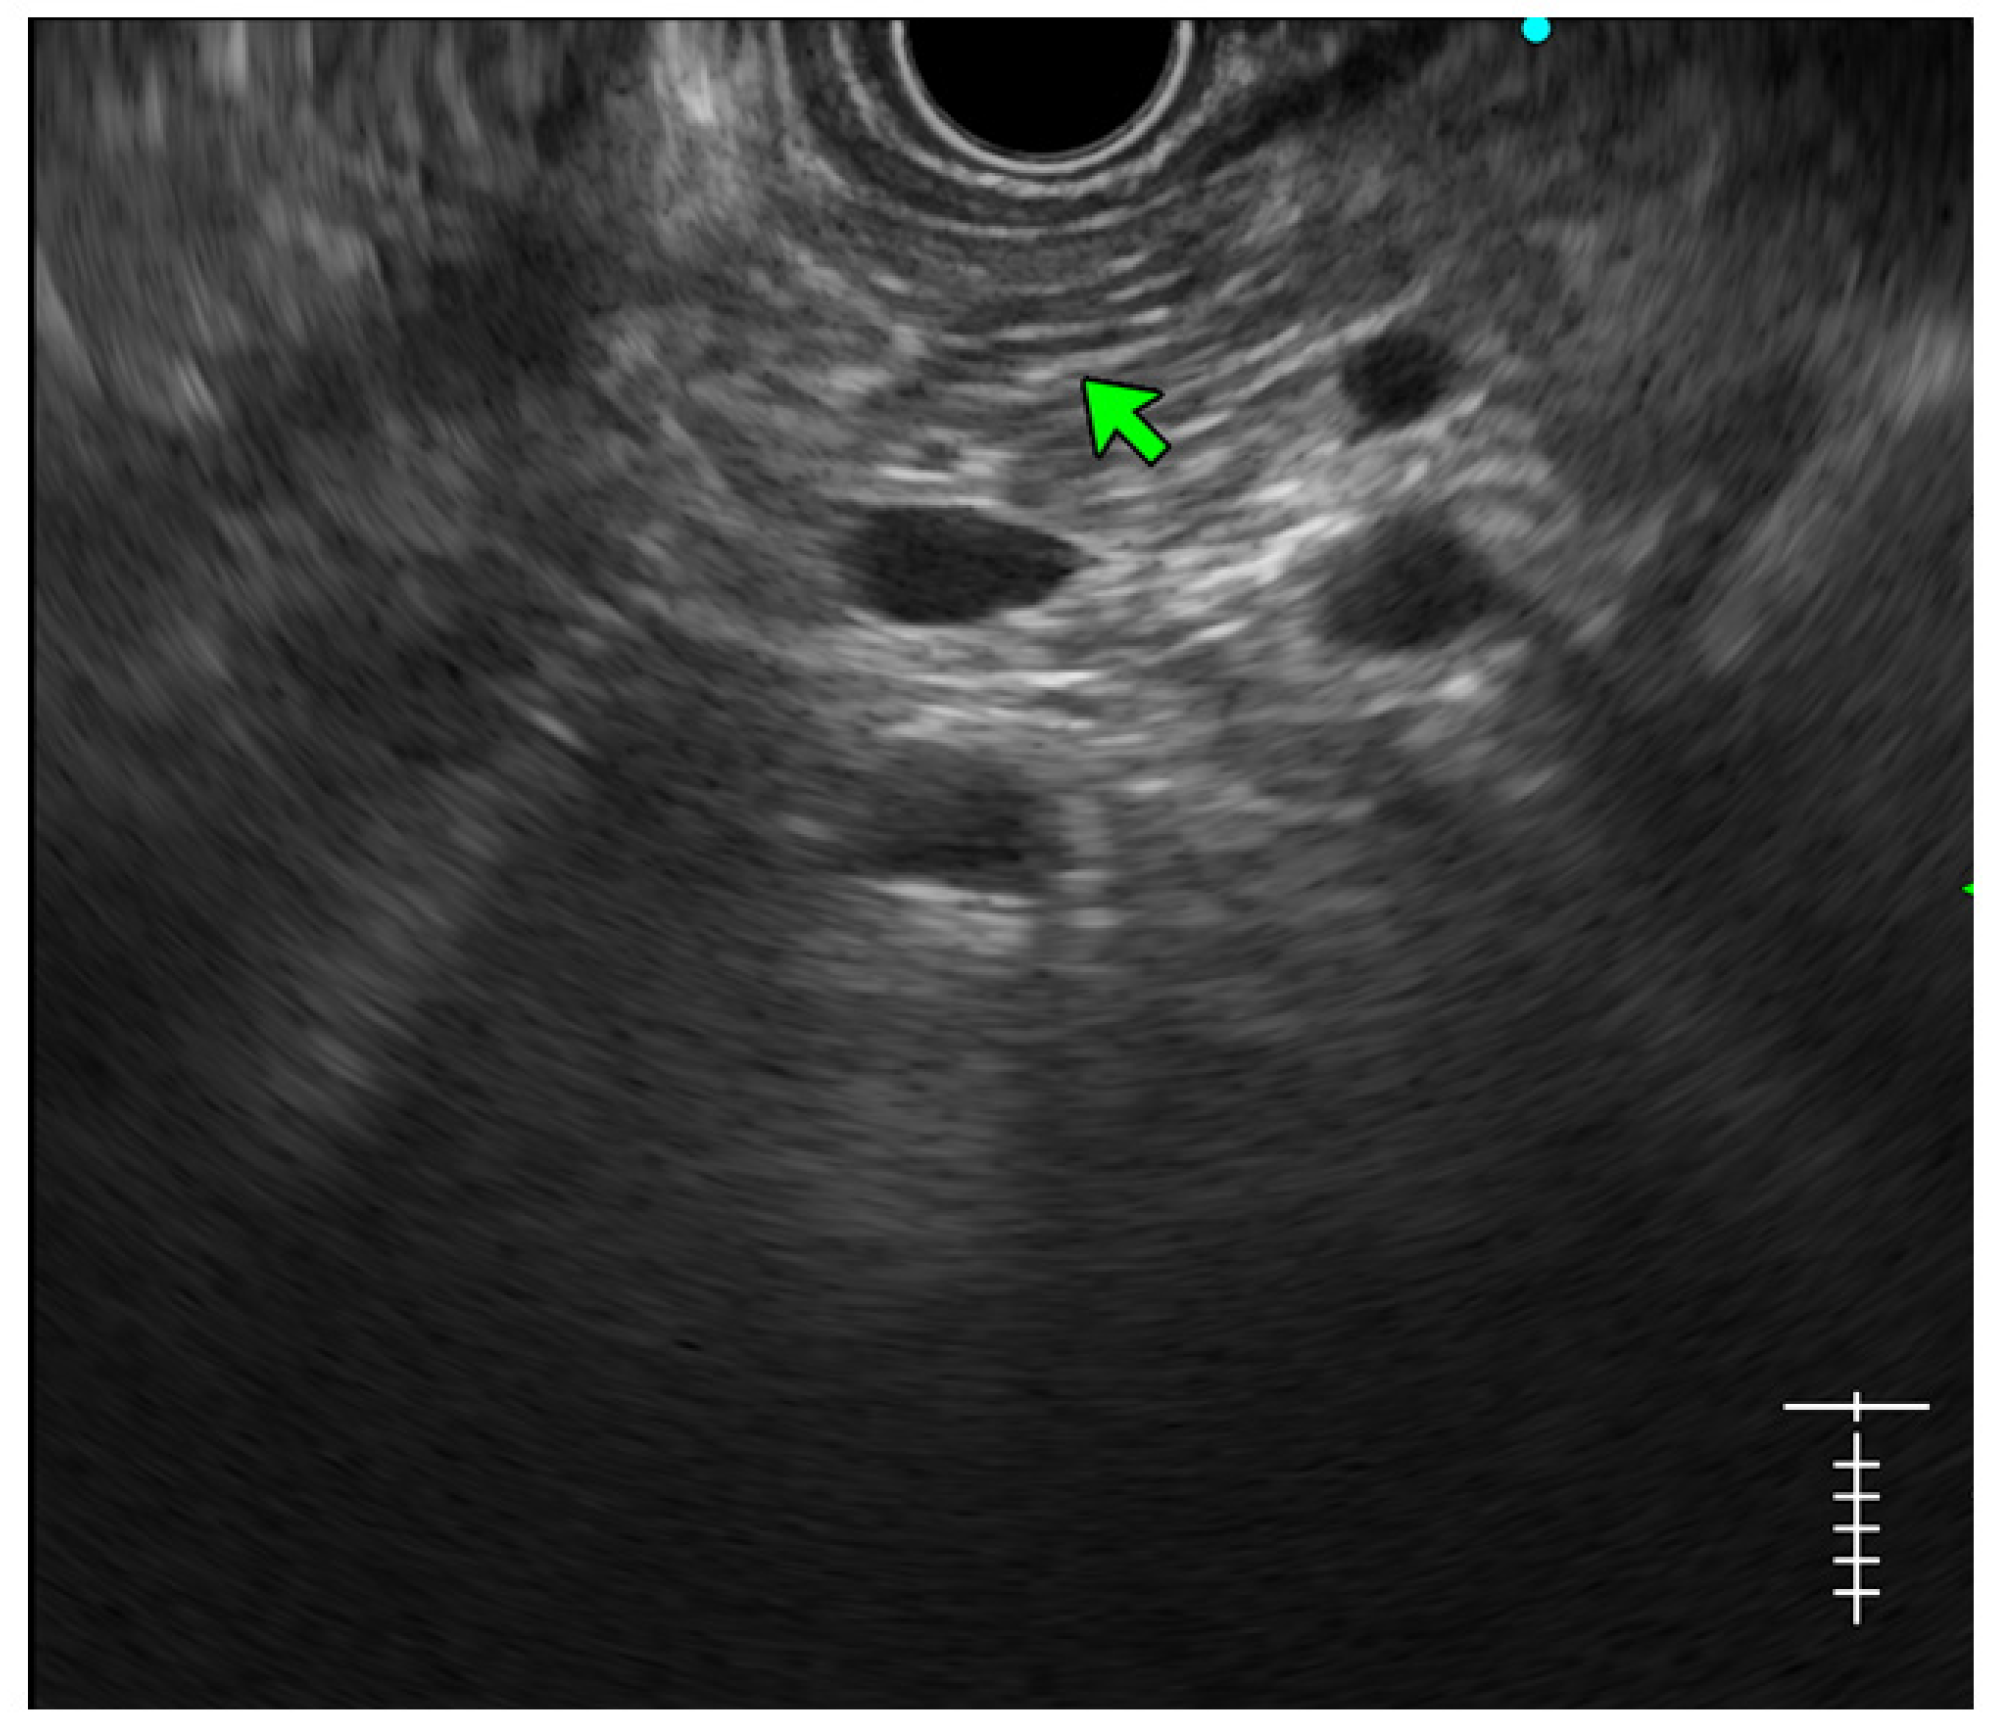

- Dilatation of the side branches: It is defined as the presence of ≥3 anechoic, tubular structures communicating with the MPD, each ≥1 mm in width, demonstrable in the body and tail region. Histologically, they correspond to the narrowing of the branch ducts due to micro-fibrosis;

- Cysts: In EUS, they are described as anechoic structures, with/without septations, round or elliptical in shape, measuring ≥2 mm in short axis. Histologically, they correspond to pseudocysts or retention cysts;